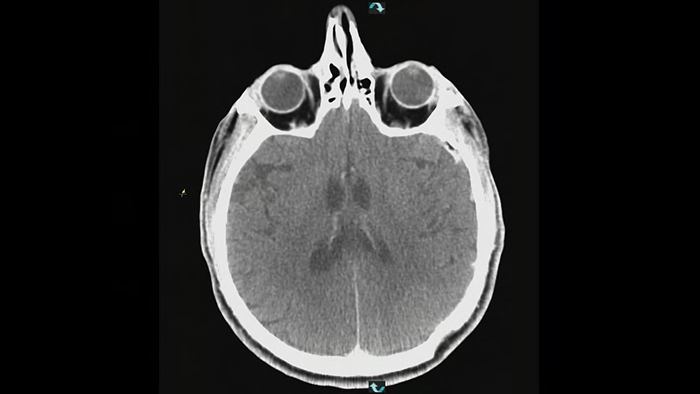

SmartCT Angio provides a volumetric view in a few seconds2 to assist assessment of feeding arteries, draining veins, arterialized veins, nidus and ruptured or unruptured pathology to guide decision making. 3D volumes are visualized with high spatial resolution and automatic patient movement compensation to enhance visibility of critical details.

SmartCT Vaso provides high resolution 3D imaging that reveals key information about cerebral vascular structures to support the highest possible spatial assessment of vessels in the soft tissue context.

SmartCT Soft Tissue is an acquisition technique that generates a CT-like visualization of soft tissue in relation to other structures during procedures. You can use the CT-like images to assess soft tissue after an AVM to check the final result and potential bleedings when the patient is still on the table.